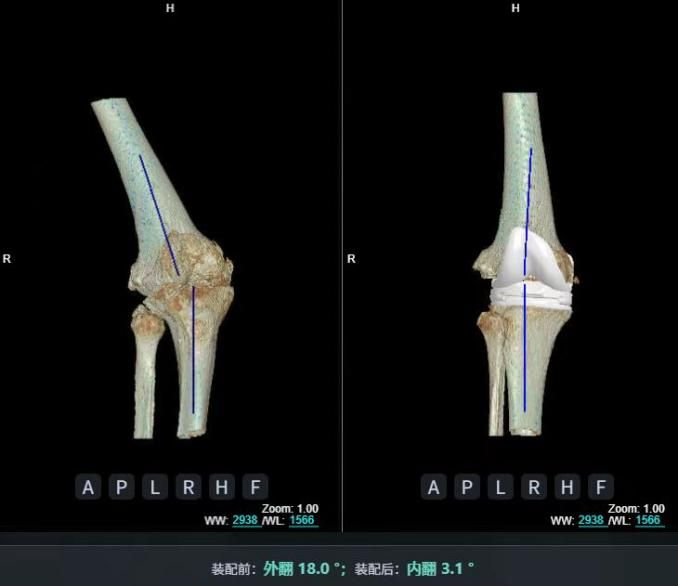

4.2 APTT-HTO脛骨高位截骨術

2025年7月,貴州醫科大學附屬醫院骨科團隊原創研發的腘肌前結節中脛骨高位截骨保膝術(Anterior Popliteus Transtibial Tuberosity-High Tibial Osteotomy, APTT-HTO)及其提出的脛骨結節分區與腘肌保護理論,登上了國際頂尖學術舞臺。該成果在全球最具影響力的專業會議之一——日本骨科協會第98屆年會上進行了兩次學術發言。[8]

貴州醫科大學附屬醫院骨科團隊

該手術具有經皮微創、保留原生膝關節結構、符合階梯治療原則等優勢,通過調整下肢力線可促進部分軟骨再生,術后關節功能接近正常(如下蹲、爬山),患者還能從事中重體力勞動。相比其他術式,其有效規避了髕骨低位、血管損傷、合頁骨折等潛在并發癥。

目前,APTT-HTO技術已成功應用于千余名患者,幫助保留自身膝關節。此類保膝手術適用于單間室膝關節炎患者(如 “羅圈腿”),核心是通過調整力線糾正畸形,減輕磨損間室壓力、發揮健康間室作用,延長膝關節壽命。若出現膝關節疼痛、保守治療無效且X線顯示關節間隙部分狹窄,建議及時就醫評估是否適合手術。

APTT-HTO脛骨高位截骨術